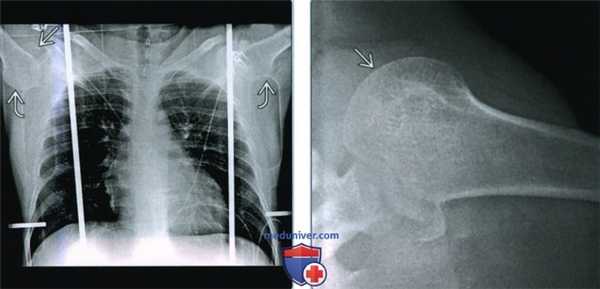

(Слева) На передне-задней рентгенограмме определяется нижний вывих головки плеча относительно суставной впадины. Плечевая кость параллельна ости лопатки, что является частым положением при luxatio erecta. Кроме того, виден фрагмент перелома большого бугорка.

(Справа) На передне-задней 3D КТ у этого же пациента определяется нижний вывих головки плеча относительно суставной впадины. Рука отведена, что является диагностическим признаком при luxatio erecta. Здесь также виден перелом большого бугорка.

(Слева) На передне-задней рентгенограмме у пациента с двусторонним luxatio erecta видна как вывихнутая книзу головка плечевой кости, так и отведенные руки, благодаря чему плечи параллельны остям лопатки. В правом плечевом суставе определяется перелом большого бугорка.

(Справа) На аксиллярной рентгенограмме левого плечевого сустава у этого же пациента визуализируется головка плеча, увеличенная за счет нижнего (и несколько переднего) вывиха, отдаляющею ее от рентгеновской пластинки.

2. Рентгенография при нижнем вывихе плеча:

• Передне-задняя проекция:

о Головка плечевой кости ниже суставной впадины

о Рука в положении максимального отведения

о Может быть перелом большого бугорка со смещением